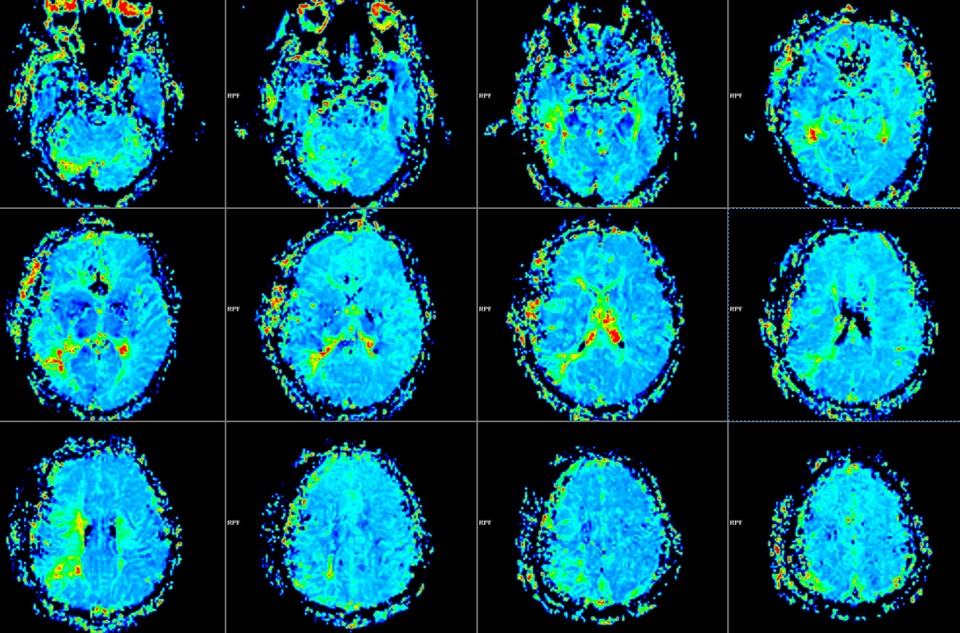

PWI显示:右侧颞叶、半卵圆区、顶下小叶MTT延长。